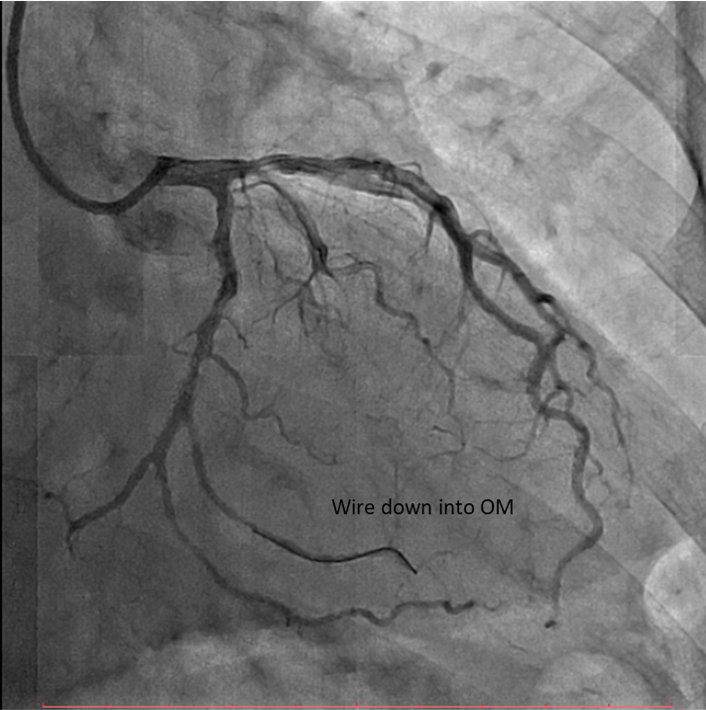

Percutaneous coronary intervention (PCI) was performed via transradial approach with 6 Fr radial sheath. Left coronary system was engaged using EBU 3.0 6 Fr guiding catheter. We decided for antegrade approach. Initial attempt with Fielder XT-A wire with a microcatheter support failed to cross the in-stent restenosis (ISR) lesion. We escalated to Asahi Gaia Second wire and successfully crossed the lesion to OM branch. Subsequently, wire was exchanged to a workhorse wire Runthrough Floppy via microcatheter. Lesion site was first predilated with a semi-compliant balloon Pantera Pro 2.0x 15 mm. Then, IVUS was passed down which showed previous stent site undersized, vessel size distal LCX of 4.0 mm. We further predilated lesion site with scoring balloon Scoreflex Trio 3.5x15 mm, up to 22 atm. Lesion site was acceptably prepared, then Paclitaxel drug-coated balloon Prevail 4.0x25 mm was deployed at nominal 6 atm for 60 seconds. Repeated IVUS run showed good stent apposition with MSA of 9.5mm2 proximally and 6.6mm2 distally. Final fluoroscopic shot showed good result with TIMI 3 flow, no stent edge dissection. Patient was symptom-free after procedure and discharged the following day.